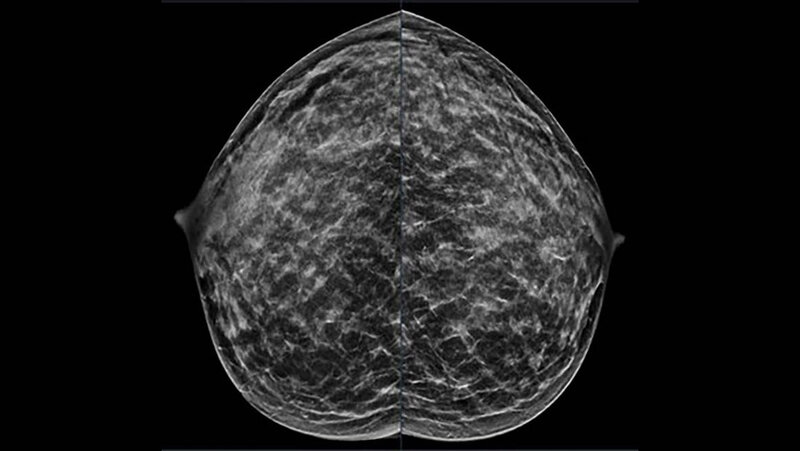

Es wurde betont, dass neue Trends in den USA darauf hindeuten, dass es eine steigende Brustkrebsrate bei jüngeren Frauen geben könnte. Empfohlen wird deshalb eine Überprüfung der altersbasierten Screening-Grenzwerte und Risikostratifizierungsstrategien. Für Frauen mit durchschnittlichem Risiko empfiehlt die U.S. Preventive Services Task Force eine Mammografie-Vorsorgeuntersuchung alle zwei Jahre ab dem 40. Lebensjahr bis zum 74. Lebensjahr. Die American Cancer Society rät zu jährlichen Screening-Mammografien ab dem 45. Lebensjahr, wobei der Beginn zwischen 40 und 44 Jahren möglich ist. Frauen mit einem erhöhten Brustkrebsrisiko aufgrund bestimmter Faktoren können von einer jährlichen Brust-MRT und Mammografie profitieren, in der Regel ab dem 30. Lebensjahr. Für jüngere Frauen gebe es derzeit keine entsprechenden Leitlinien, so die RSNA.

Dr. Destounis und ihre Kollegin Andrea L. Arieno, B.S., Forschungsleiterin bei EWBC, untersuchten in einer Gemeinschaftspraxis mit sieben ambulanten Einrichtungen im Umkreis von 320 Kilometern (200 Meilen) in der Region Western New York alle Brustkrebsfälle, die zwischen 2014 und 2024 diagnostiziert wurden. Sie erfassten alle Brustkrebsfälle in der Altersgruppe der 18- bis 49-Jährigen und sammelten Informationen aus klinischen Bildgebungsberichten. „Wir haben gezielt Informationen darüber gesammelt, wie der Krebs entdeckt wurde (Screening oder diagnostische Untersuchung), um welche Krebsart es sich handelte und welche anderen Tumoreigenschaften vorlagen“, sagte Dr. Destounis. „Wir schlossen Fälle aus, die kein primärer Brustkrebs waren. Wir analysierten die zeitlichen Trends nach Altersgruppen, Entdeckungsmethode und Tumorbiologie. Dies half uns, zu ermitteln, wie sich Brustkrebs in dieser Patientengruppe manifestiert, wie häufig er auftritt und welche Tumorarten gefunden wurden.“